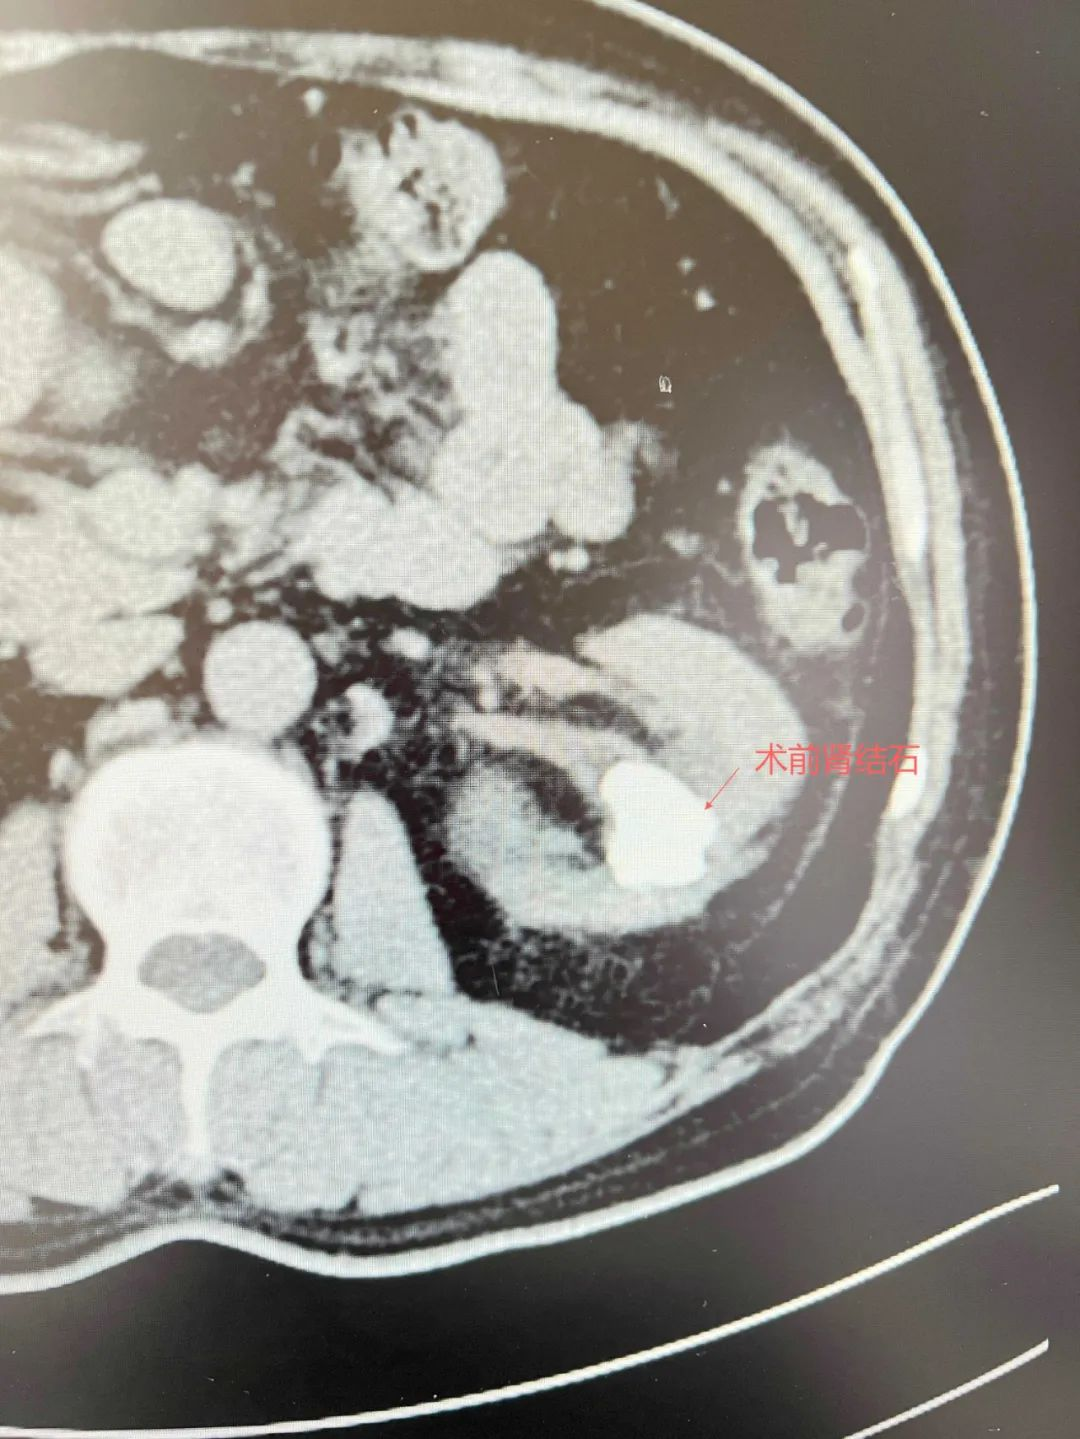

▲术前CT片

向先生患有左肾多发结石多年,曾在四川当地医院接受多次开放式手术和输尿管镜手术,但结石残留问题始终反复,未能彻底解决,最大残留结石直径达5厘米。更为凶险的是,结石频繁脱落引发输尿管梗阻,导致多次感染性休克,曾到ICU抢救。即便在四川某顶级三甲医院,专家也摇头叹息:“肾脏结构复杂如迷宫,常规手段已无能为力”。就在向先生近乎绝望时,他偶然得知广东省人民医院泌尿外科专家毕学成主任正在我院开展帮扶工作,当即决定跨越1600公里,从四川乘飞机辗转至广州,再转车奔赴河源。

面对这一复杂病例,毕学成主任带领泌尿外科团队迅速制定治疗方案。经详细检查发现,患者左肾结石不仅体积大、数量多,由于经历多次手术,结石与肾实质形成“钢筋混凝土”式粘连,传统术式极易引发大出血。毕学成主任带领多学科团队采用“经皮肾镜+输尿管软镜双镜联合术式”:先在超声引导下建立0.6厘米微创通道粉碎主体结石,再通过自然腔道置入输尿管软镜清除死角残石。两台高精设备“天地配合”,仅历时2小时将结石彻底“剿灭”,术中出血仅50毫升。术后复查显示患者左肾结石100%清除,困扰多年的腰痛、感染症状彻底消失。术后次日,向先生就可以下床活动,向先生激动表示:“跑了那么多医院,只有这里给了我重生的希望!感谢毕主任和团队的高超技术!”